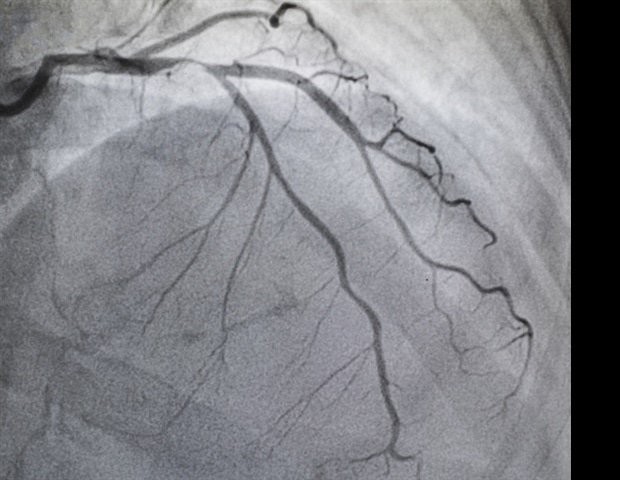

MAC occurs when calcium builds up in a ring of tissue known as the annulus, which supports the heart’s mitral valve. This buildup can affect how the valve closes, leading to complications such as symptomatic mitral regurgitation, where blood flows backwards toward the heart, leading to a reduced quality of life. Patients with severe symptoms who are considered high risk for surgery may undergo M-TEER. M-TEER is a minimally invasive procedure that places a small clip on the mitral valve to help it close more tightly and reduce the amount of blood flowing back into the heart. There is limited evidence regarding the feasibility and outcomes of M-TEER in patients with MAC.

For the EXPANDed trial, researchers analyzed data from the EXPAND and EXPAND G4 trials, which included patients who received M-TEER with the MitraClip™ G3 or G4 system (Abbott) at 91 sites in the United States, Europe, Canada, the Middle East, and Japan between 2018 and 2022. Of the 1,907 patients who participated, 327 had MAC. These patients were older, had a higher surgical risk, had a higher prevalence of primary MR, and were more likely to be female. Additionally, half of the patients in both groups had been hospitalized for heart failure within the previous year.

This study found that the acute surgical success rate was higher in the calcification-free group (96% vs. 92%). All-cause mortality was higher in the MAC group at 30 days (3.4% vs. 1.7%, p=0.04) and at 1 year (18.3% vs. 12.1%, p=0.003). MAC patients also had a higher rate of heart failure hospitalization after 1 year (24.2% vs. 16.4%, p=0.001). In both groups, exchange rates were low and there were no safety concerns throughout the year, including single-leaflet device attachment, myocardial infarction, and stroke. The reduction in MR was similar, with 87.9% of MAC patients and 91.3% of non-MAC patients being ≤1+ at 1 year. Quality of life also significantly improved in both groups and was maintained throughout the year, with 81% of patients having mild or no symptoms during normal activities (defined as NYHA class I/II). Patients also experienced a significant increase in KCCQ-OS (Kansas City Cardiomyopathy Questionnaire – Global Overview, which measures how heart failure patients feel and function in daily life) scores (21.8 ± 26.3 with MAC and 19.0 ± 24.5 without MAC).

It is known that the presence of mitral annular calcification may complicate mitral valve disease. However, this first large-scale real-world study shows that MitraClip surgery is a safe and effective option for patients with severe symptoms, leading to significant reductions in mitral regurgitation and significant improvements in quality of life, regardless of the presence or absence of MAC. The observed differences in 1-year mortality and heart failure hospitalization likely reflect the burden and complexity of comorbidities in patients with MAC compared with those without calcification. ”